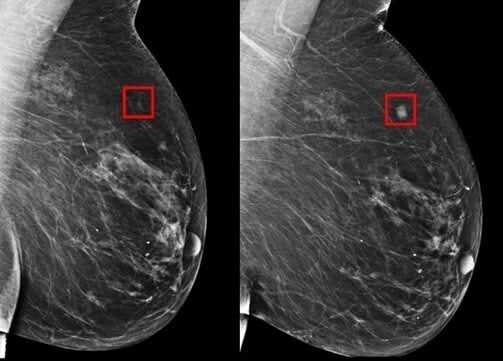

A inteligência artificial que pode salvar milhões de vidas O crescente avanço da tecnologia, em especial na medicina, tem trazido esperanças significativas para a detecção precoce de doenças graves. A inteligência artificial (IA) tem sido uma grande aliada na identificação de sinais de câncer de mama, podendo detectar a doença até cinco anos antes do …